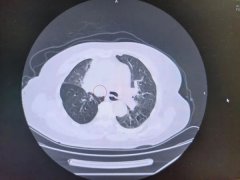

气管被肿瘤“封喉”,多学科协作破局,为晚期肺癌患者抢出“生机”

当生命的呼吸通道 被肿瘤无情扼住咽喉 每一秒 都是生与死的较量 近日,南通六院肿瘤科、介入科、呼吸与危重症医学科联合上演了一场生命接力,通...